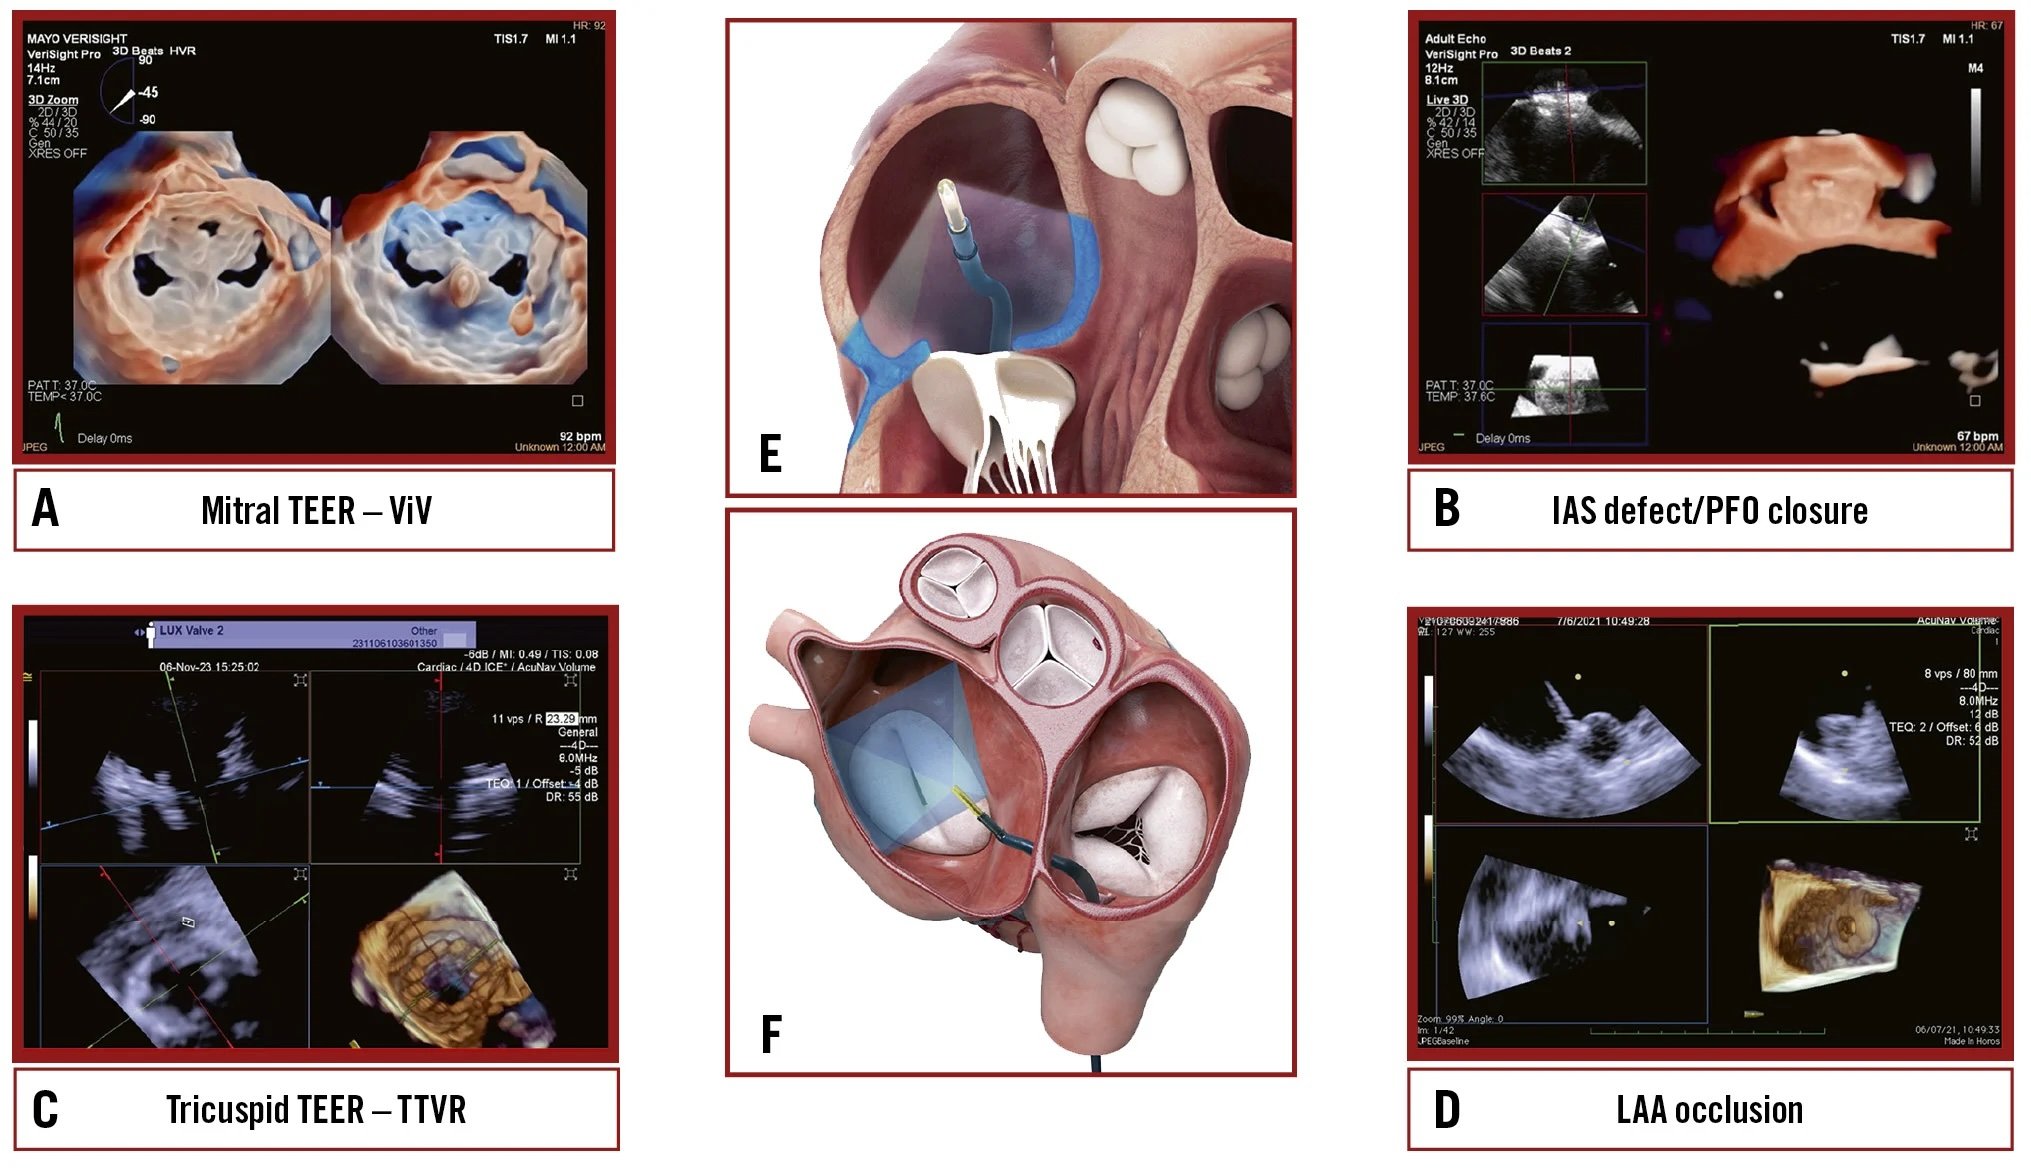

A 73-year-old female with a history of rheumatic fever and severe mitral stenosis who had undergone TMVR presented with severe tricuspid regurgitation. 3D ICE-guided TTVR was performed, with a successful outcome.

A State-of-the-Art on TAVI thrombosis; a novel stress aortic valve index; design and rationale of the SURVIV trial; extended-length introducer sheaths for TAVI; leaflet avulsion after UNICORN leaflet modification; 3D intracardiac echo-guided transcatheter tricuspid valve replacement; and more